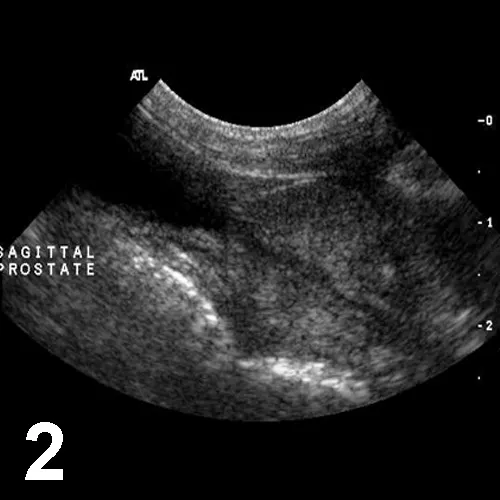

Abdominal ultrasonography—including both inguinal canals to the extent that was possible—disclosed no abnormalities, including presence of an abdominal testis. The prostate appeared enlarged and hyperechoic—typical of a mature male (Figures 1 and 2).

Figure 2. Sagittal image of a normal prostate in an intact dog; note the increased echogenicity of the prostatic parenchyma